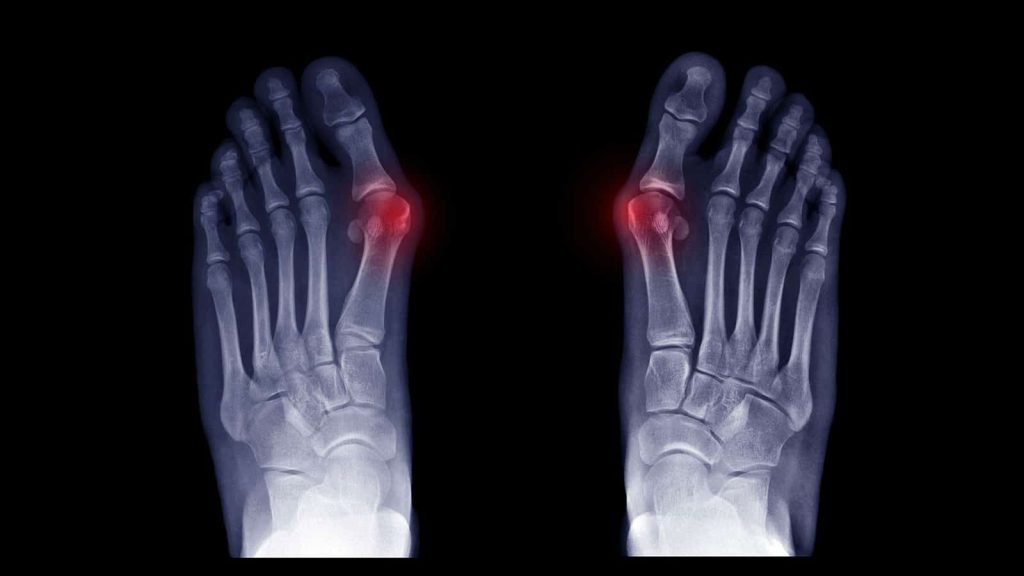

Bunions are a common foot problem that is accompanied by symptoms including pain and a bony growth that turns into a large lump.

Regular checks and x-rays are recommended to prevent joint damage. Treatment options include changes in foot wear, orthotics, regular exercise, padding and active modifications such as standing or walking for long periods of time.

A bunion is a bony bump that forms at the base of the big toe where it meets the foot. The big toe may start to angle toward the second toe, and you may notice a visible lump, redness, swelling or rubbing in shoes. If you are unsure, a podiatry assessment can confirm whether you have a bunion and how advanced it is.